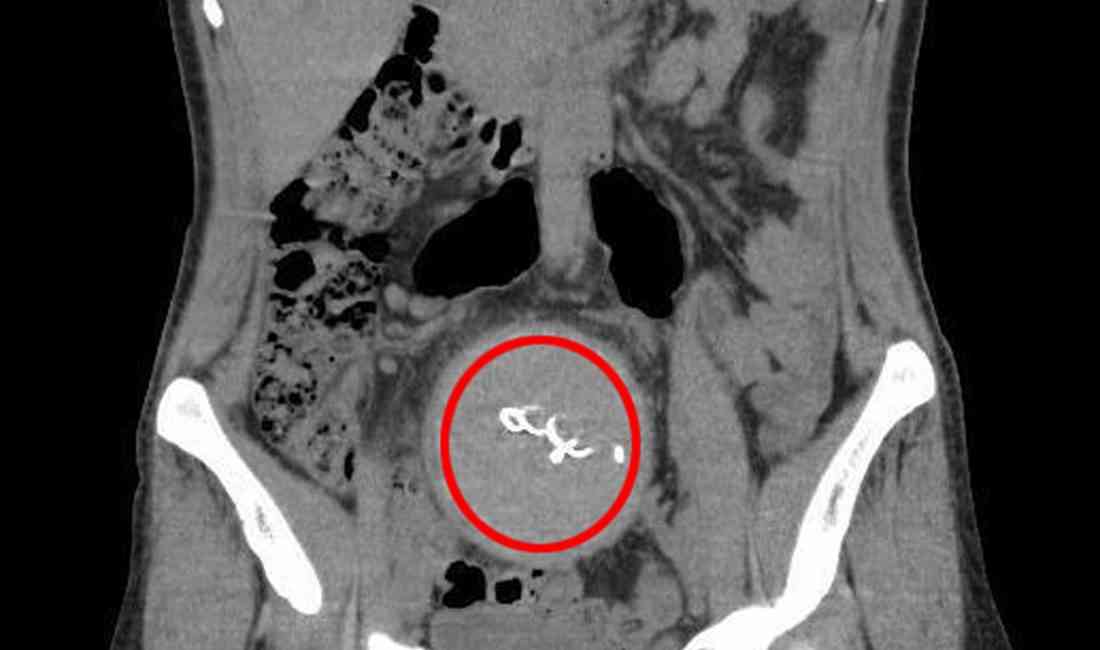

Antalya’da, 2021 yılında özel bir hastanede sezaryenle doğum yapan Y.S. (34), 2 yıl süresince yaşadığı ağrılar ve iltihap akıntısı nedeniyle şok edici bir gerçekle karşılaştı. Y.S., hastaneye başvurduğunda yapılan tomografi sonucunda, doğum sırasında vücudunda unutulan yaklaşık 30 santimetre uzunluğunda bir gazlı bezin kaldığı tespit edildi.

Y.S., doğum sonrası yaşadığı şiddetli ağrı ve iltihap nedeniyle hastaneye tekrar başvurdu. İlk başvurularında, doğumunu yapan doktoru D.A., durumun normal olduğunu belirterek tedaviye devam etti. Ancak ağrılar ve iltihaplar geçmeyince Y.S. başka hastanelere başvurdu, ancak çözüm bulamadı. 2 yıl süren sıkıntılarının ardından 2023 yılında Antalya Eğitim ve Araştırma Hastanesi’ne başvuran Y.S., burada yapılan tomografide, doğum sırasında unutulan gazlı bezin vücudunda kaldığı ortaya çıktı. Y.S., bu ihmalin tıbbi hataya yol açtığını belirterek hastane ve sorumlu doktorlar hakkında savcılığa suç duyurusunda bulundu.

Ameliyat sonrası malzeme sayımı ve raporlama konusunda eksiklikler olduğu ifade edilirken, hastanın vücudunda unutulan yabancı cismin, bağırsak tıkanıklığına neden olduğu ve bu durumun tanısal gecikmeye yol açtığı belirtildi. Sağlık Bakanlığı tarafından yapılan incelemede, 4 sağlık personelinin eylemlerinin adli mercilerle aydınlatılmasına karar verildi. Bu personeller arasında doğum yapan doktor D.A., ameliyathane hemşiresi Ö.Ö. ve diğer uzman doktorlar yer aldı.